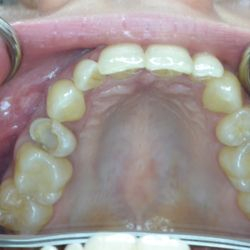

Ο 43χρονος αυτός ασθενής προσήλθε στο ιατρείο μας με έντονες αποτριβές των προσθίων και οπισθίων δοντιών του.

Ο αιτιολογικός παράγοντας για την καταστροφή της οδοντικής του ουσίας ήταν τα γαστρικά οξέα λόγω της χρόνιας γαστρο-οισοφαγικής παλινδρόμησης που παρουσίαζε.

Τα πρόσθια δόντια του αποκαταστάθηκαν με χτίσιμο σύνθετης ρητίνης επί τόπου ενώ τα οπίσθια δόντια του αποκαταστάσθηκαν με εργαστηριακά κατασκευασμένα επένθετα σύνθετης ρητίνης